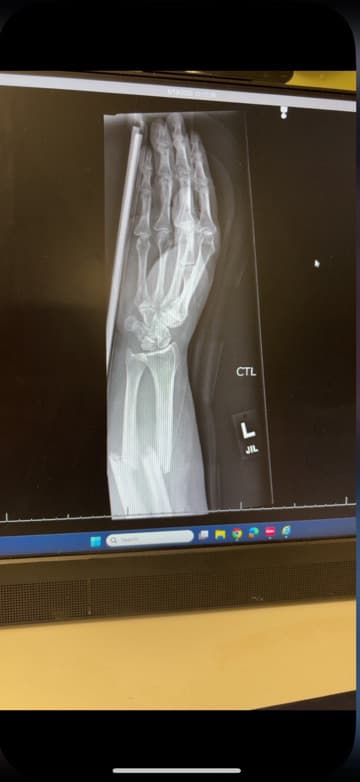

My mom and I spoke about how would I know if she was near me after she had passed ? What would be my “sign”? Jokingly I said send me gray feathers . I forgot all about that conversation until I broke my arm. I broke both bones in my forearm and was flown to a larger hospital. As they were putting me in the helicopter the on flight nurse said oh you have a feather in your hair …. That’s the first time I started crying. I knew my mom was with me. I still have the feathers . This is my lovely broken arm. I have plates and screws now 🤦♀️